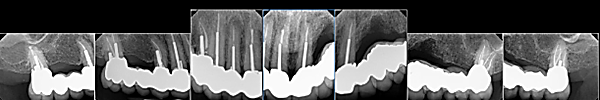

Mrs. B was referred by her periodontist after her three upper left implants failed, leaving no bone to support replacements (Fig. 1). She explicitly did not want a denture or All-on-X. To meet her needs, we designed and placed a full arch of meticulously splinted crowns on her natural teeth (Fig. 2), delivering a fixed prosthesis with excellent long-term prognosis. X-rays at six years confirm the reconstruction remains stable (Fig. 3).

Fig. 1: Patient’s Upper Left Implants Failed Leaving No Bone

Fig. 2: Reconstruction with Splinted Crowns and No Removable Appliance

Fig. 3: X-Rays Showing the Full Upper Reconstruction Permanently Cemented Six Years After Completion